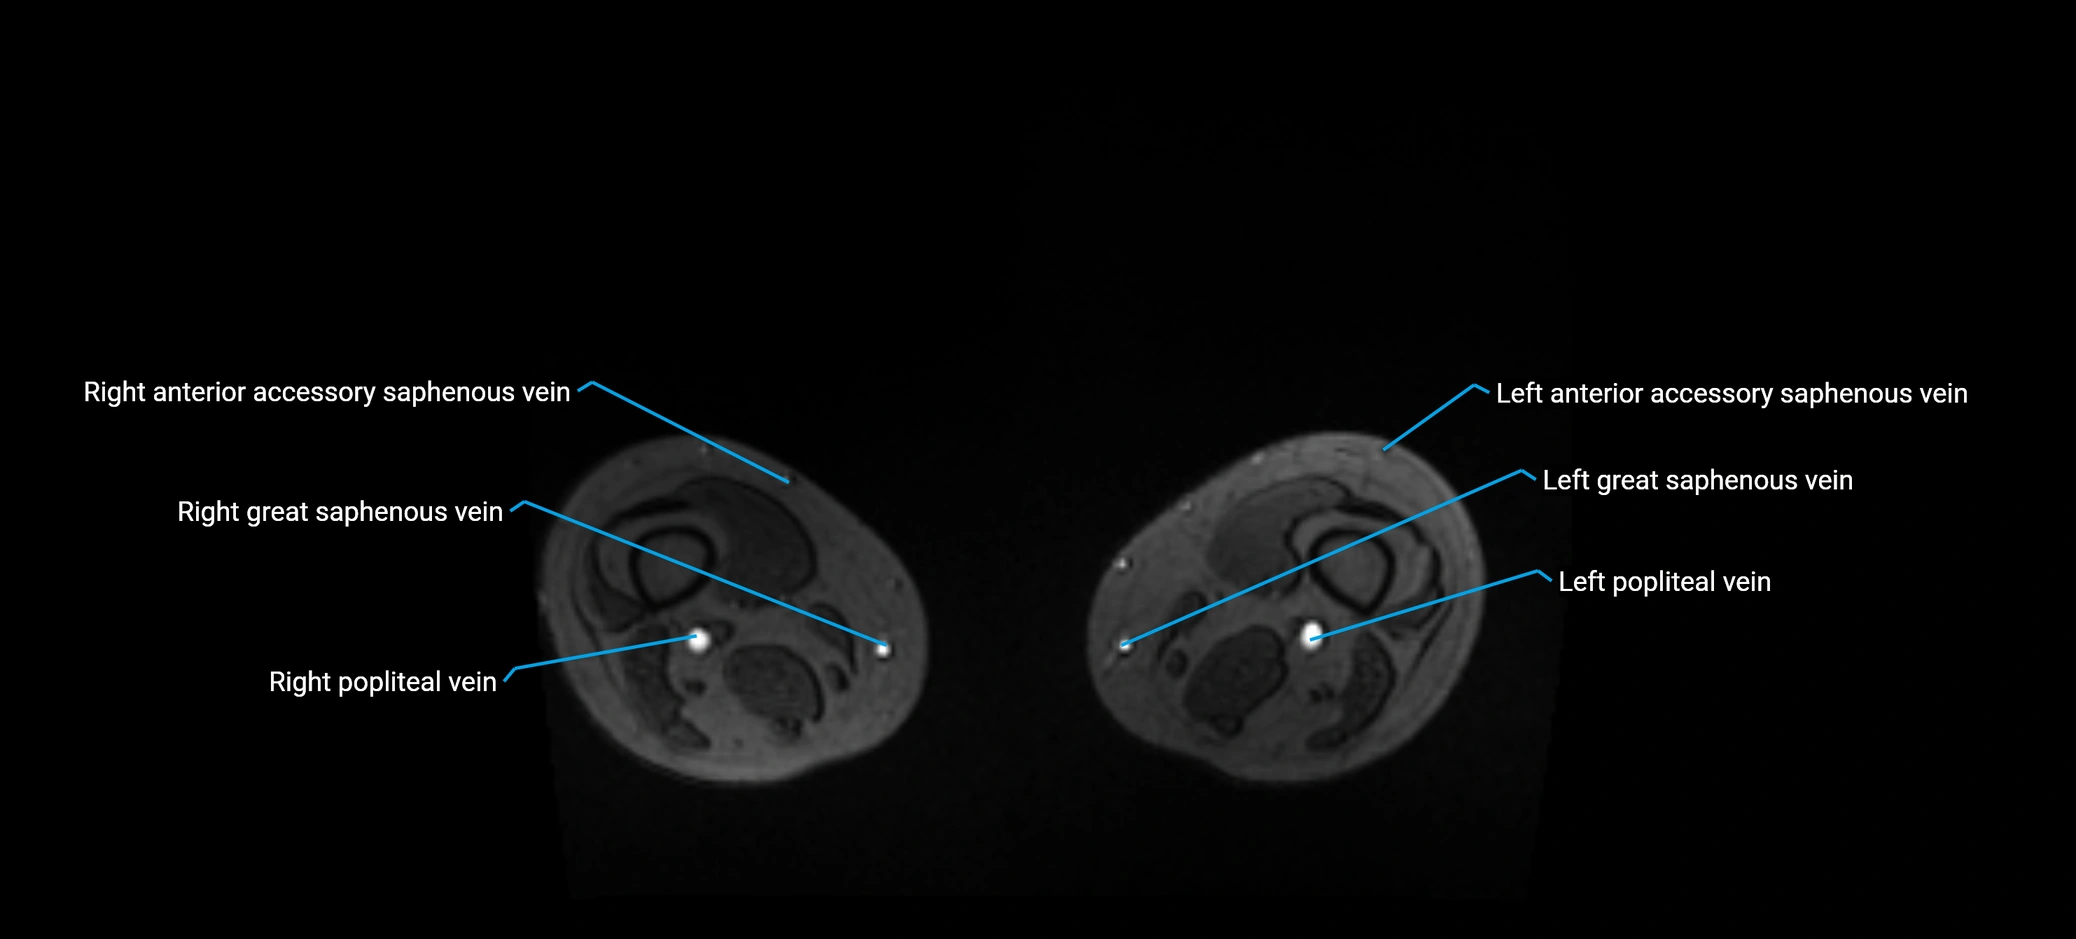

MRI image

image